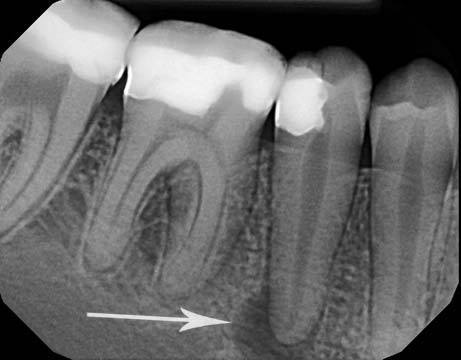

1. DIAGNOSIS

1. DETERMINATED BY

1. EXAM AND TEST

1. X-RAY RESULTS